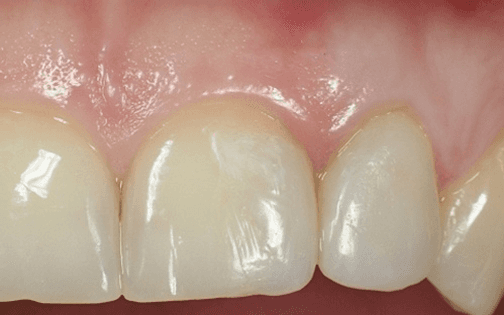

Il restauro definitivo sul dente laterale: notare la buona integrazione fra il dente e il restauro.

Il laterale di sinistra dopo la rimozione del vecchio restauro. Anche in questo caso tutto il tessuto sano della paziente è stato mantenuto.

Il laterale di sinistra ultimato.